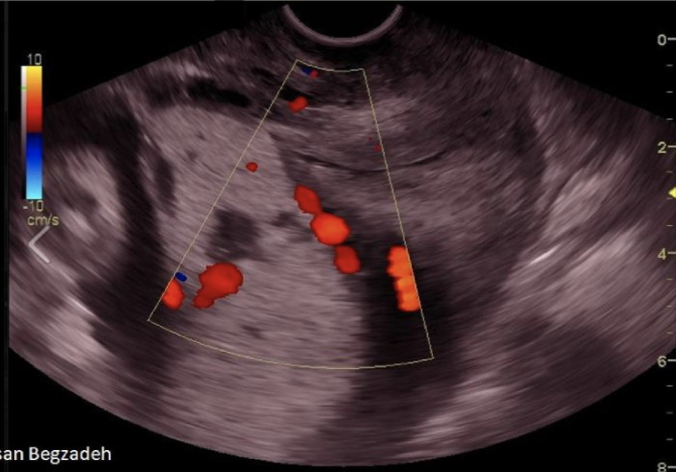

chorioangioma is supected. which image shows it

a) A

b) B

c) C

d) D